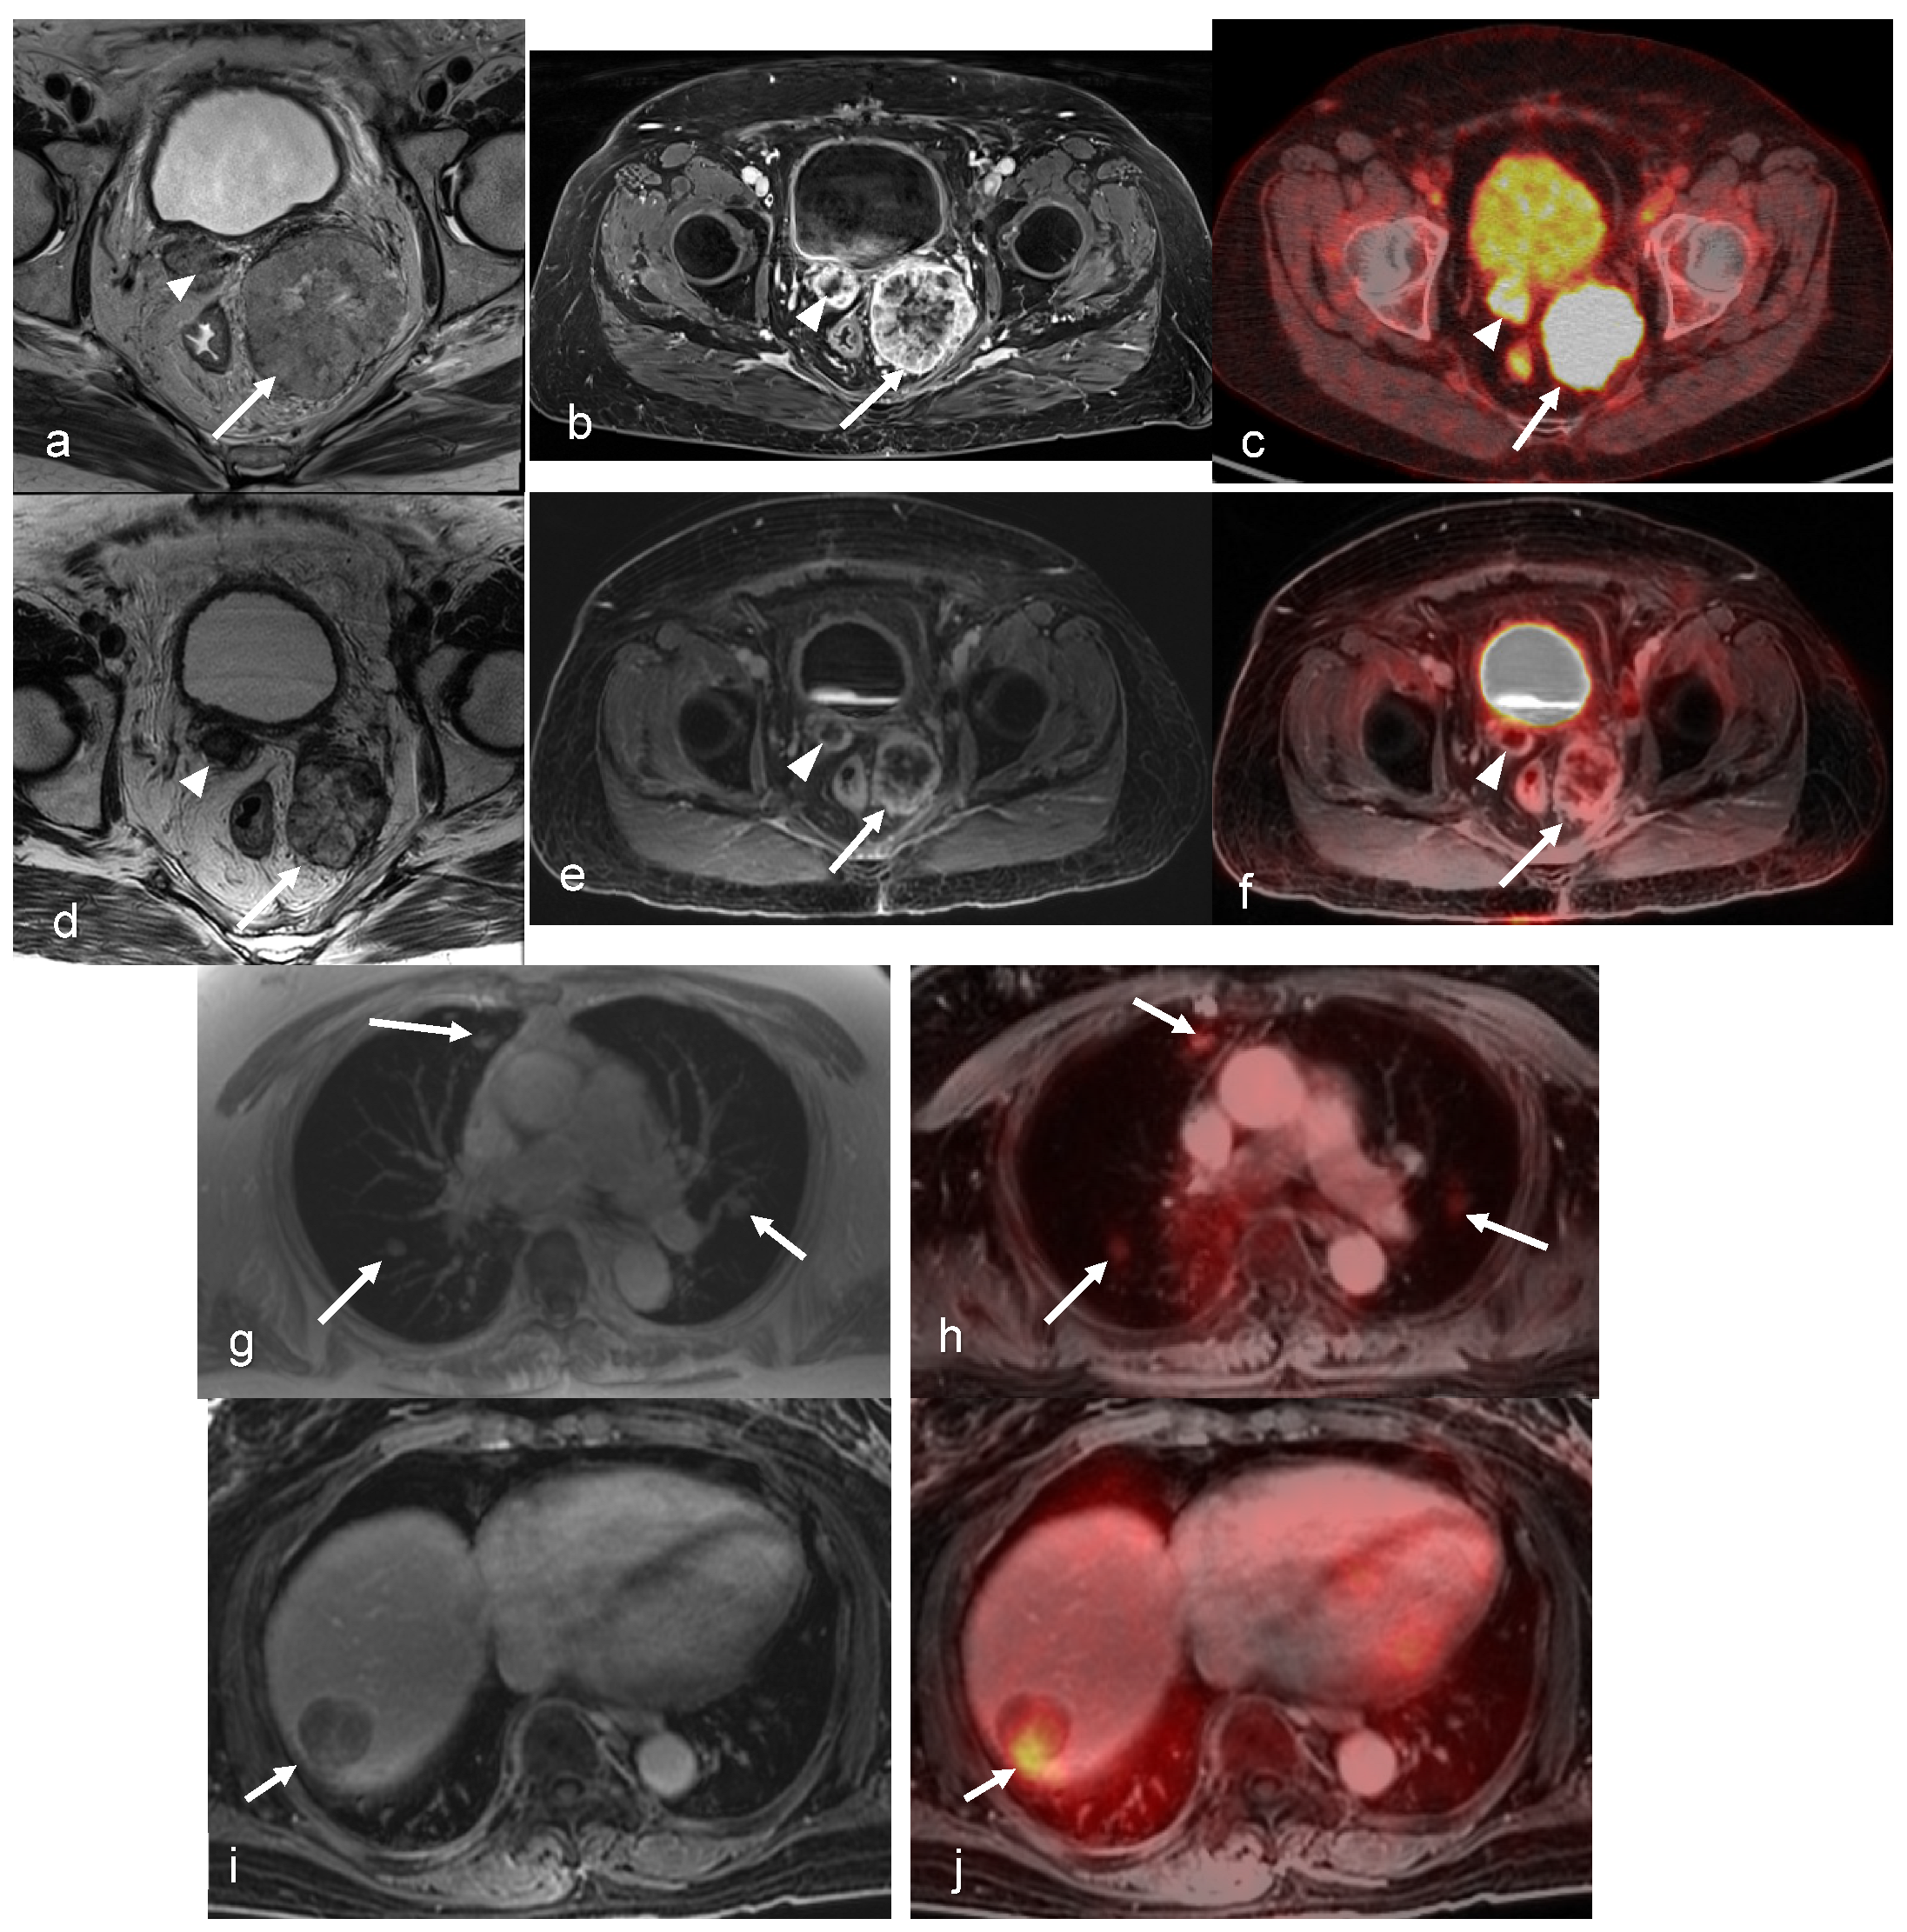

3.1. Cervical Cancer

- Grueneisen, J.; Schaarschmidt, B.M.; Heubner, M.; Aktas, B.; Kinner, S.; Forsting, M.; Lauenstein, T.; Ruhlmann, V.; Umutlu, L. Integrated PET/MRI for whole-body staging of patients with primary cervical cancer: Preliminary results. Eur. J. Nucl. Med. Mol. Imaging 2015, 42, 1814–1824. [Google Scholar] [CrossRef] [PubMed]

- Brandmaier, P.; Purz, S.; Bremicker, K.; Hockel, M.; Barthel, H.; Kluge, R.; Kahn, T.; Sabri, O.; Stumpp, P. Simultaneous [18F]FDG-PET/MRI: Correlation of Apparent Diffusion Coefficient (ADC) and Standardized Uptake Value (SUV) in Primary and Recurrent Cervical Cancer. PLoS ONE 2015, 10, e0141684. [Google Scholar] [CrossRef] [PubMed]

- Grueneisen, J.; Beiderwellen, K.; Heusch, P.; Buderath, P.; Aktas, B.; Gratz, M.; Forsting, M.; Lauenstein, T.; Ruhlmann, V.; Umutlu, L. Correlation of standardized uptake value and apparent diffusion coefficient in integrated whole-body PET/MRI of primary and recurrent cervical cancer. PLoS ONE 2014, 9, e96751. [Google Scholar] [CrossRef] [PubMed]

- Gong, J.; Wang, N.; Bian, L.; Wang, M.; Ye, M.; Wen, N.; Fu, M.; Fan, W.; Meng, Y. Cervical cancer evaluated with integrated 18F-FDG PET/MR. Oncol. Lett. 2019, 18, 1815–1823. [Google Scholar] [CrossRef] [PubMed]

- Queiroz, M.A.; Kubik-Huch, R.A.; Hauser, N.; Freiwald-Chilla, B.; von Schulthess, G.; Froehlich, J.M.; Veit-Haibach, P. PET/MRI and PET/CT in advanced gynaecological tumours: Initial experience and comparison. Eur. Radiol. 2015, 25, 2222–2230. [Google Scholar] [CrossRef] [PubMed]